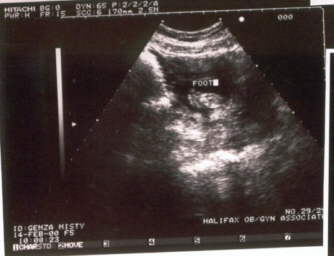

Madison at her 24wks ultrasound

A good profile......................A tiny foot.